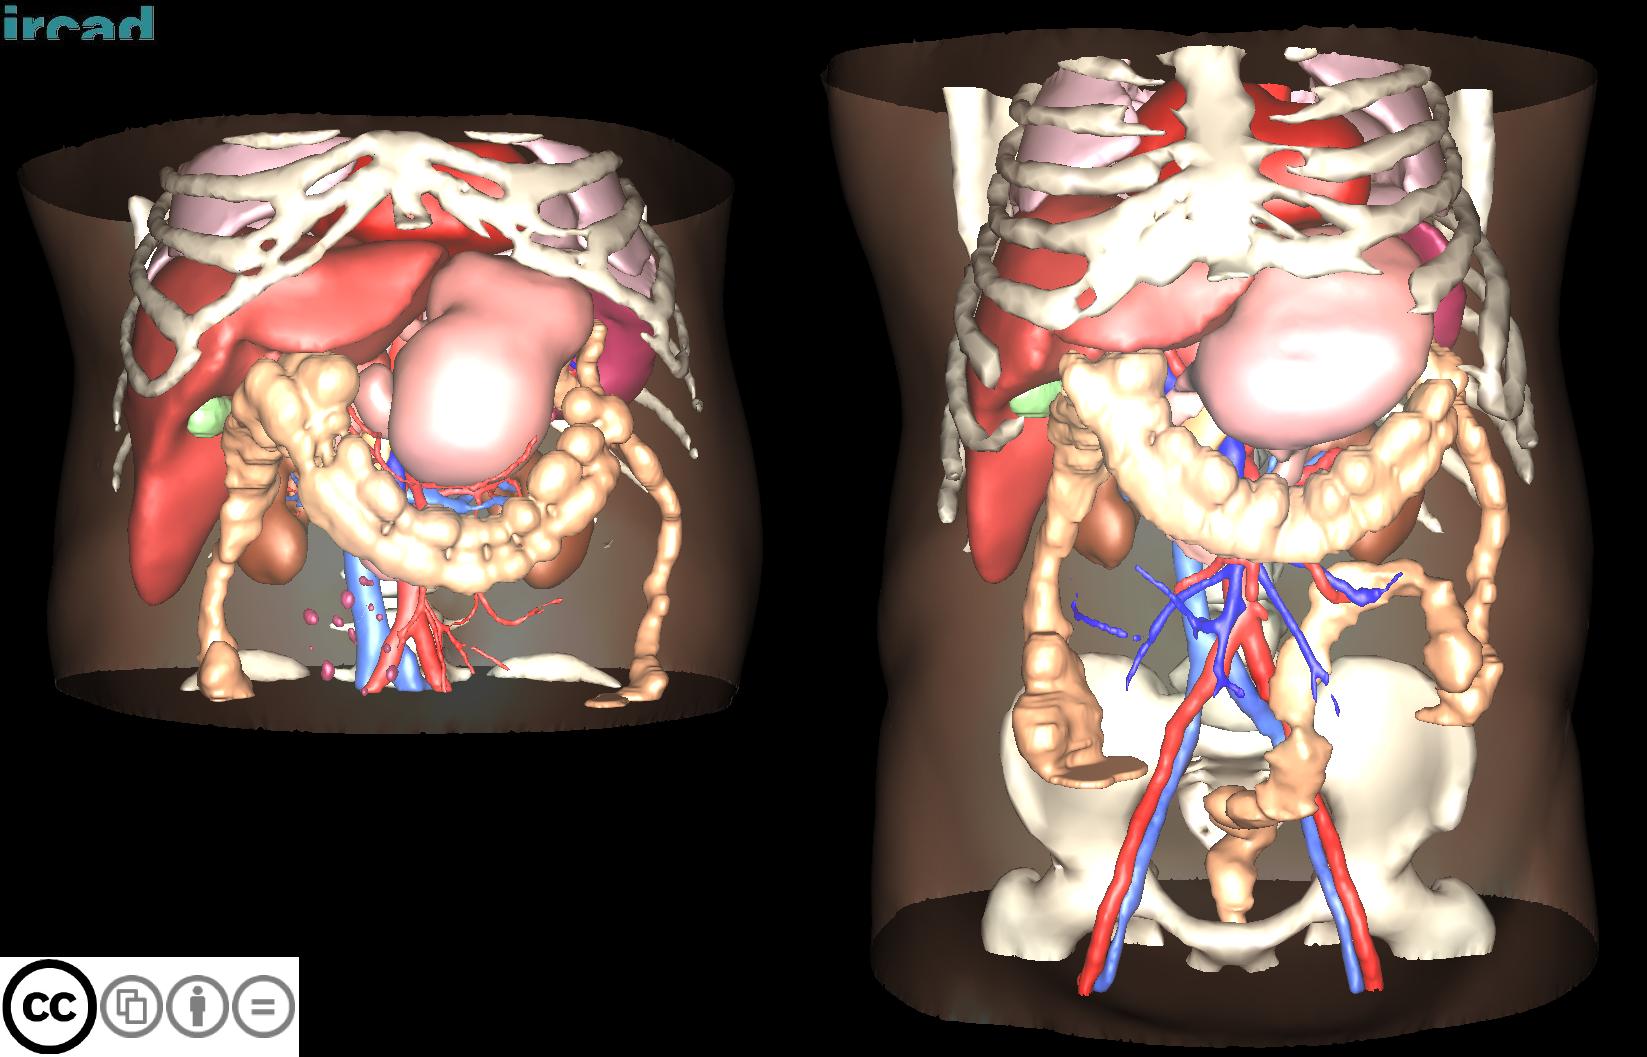

3D-IRCADB

| 3D-IRCADb 01 02 | 肝脏/肝肿瘤 | 分割 | CT | 20+2 | surface mesh | dcm |

3D-IRCADb是比较早的一个数据集,有两个子集,分别包含20组和2组CT片子。